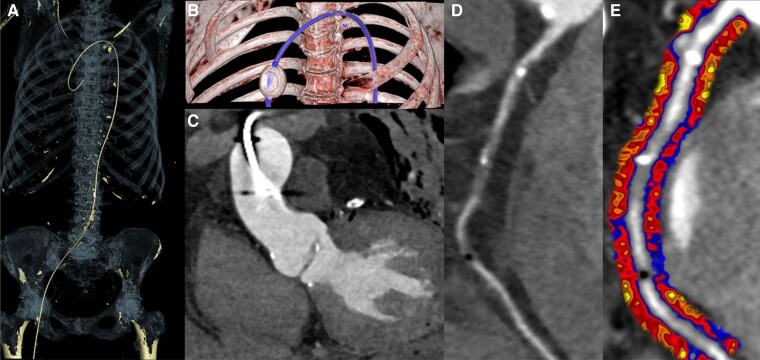

欧洲心脏病学会于2024年8月30日至9月2日在英国伦敦举行了年度大会。共有3800名参与者,5400名教师和演讲者,以及许多国家心脏协会和行业合作伙伴,大会在展示和讨论心血管医学的最新进展方面迈出了巨大的一步。在提交摘要数量最多的10个国家中,有5个来自欧洲以外的国家:中国、美国、日本、韩国和澳大利亚。这极大地推动了国际合作和意见交流,从不同的角度学习。具体来说,心血管成像领域已经成为人们关注的焦点,表明其在现代心血管医学中日益增长的、核心的和横向的作用。在本文中,我们总结了在超声心动图、心血管磁共振、计算机断层扫描和核成像四种成像方式领域内,在新颖性或临床适用性方面的一些显著研究进展。

The European Society of Cardiology has held its annual Congress in London, UK, from 30 August to 2 September 2024. With a total of 31 800 participants, 5400 faculty and presenters, and many National Cardiac Societies and industry partners, the Congress has taken an enormous step forward to present and discuss the latest advances in cardiovascular medicine. The sizable intercontinental reach was proved by the fact that 5 of the 10 top countries, in terms of submission of abstracts, were from outside Europe: China, the USA, Japan, Korea, and Australia. This brought a great impetus for international collaboration and exchange of views, learning from different perspectives. Specifically, the field of cardiovascular imaging has been in the spotlight, remarking its growing, central, and transversal role in modern cardiovascular medicine. In this communication, we offer a summary of some notable advances in research, either in terms of novelty or clinical applicability, within the realm of four imaging modalities: echocardiography, cardiovascular magnetic resonance, computed tomography, and nuclear imaging.